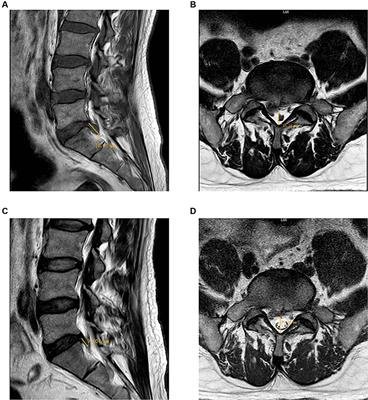

Physical examination revealed that the patient was in a compulsive position and the soft tissues of the lower back were in a state of tension. His spinal mobility was 10° anterior flexion, 5° dorsiflexion, 15° left flexion, 10° right flexion, 10° left rotation and 10° right rotation, along with bilateral spinal paraspinal muscle tenderness and radicular pain at the L4-L5 and L5-S1 levels. There was a positive sign on the Lasegue test of 30° for the right side, and positive results were also obtained for the Tinel sign and the test of supinating and throwing out his belly. His Freiberg sign and piriformis sign were both negative, ruling out the diagnosis of piriformis syndrome. Both lower limbs have normal muscle strength, tone, achilles tendon reflex and sensation, and pathological reflexes were not elicited. His back pain intensity was 9, measured on a 10-point visual analog scale (VAS), and his Japanese Orthopedic Association (JOA) score was 5. MRI demonstrated his lumbar disc was extruding downwards to the right posterior on L5-S1, protruded outwards on L3-L4 and bulged outwards on L2-L3 and L4-L5 (Figure 1). The computer PACS image workstation was applied to measure the sagittal protrusion length of the L5/S1 intervertebral disc, which was as high as 16.10 mm (Figure 1A), and the diameter of the spinal canal on the cross section was only 12.16 mm (Figure 1B). As the maximal cranio-caudal diameter of the disc fragment exceeds that of its base at the level of the parent disc, meeting the criteria for classification as an extrusion (5). Based on the above, the patient was diagnosed with extruded lumbar disc herniation.

Figure 1. Comparison of MRI of the lumbar region at the time of the initial visit (2023-02-19) and after a period of treatment (2023-05-16). (A): The sagittal view showed a herniated nucleus pulposus in the L5-S1 segment, resulting in spinal cord compression. The sagittal protrusion length of the L5/S1 intervertebral disc measured as high as 16.10 mm. (B): The axial view showed a large disc herniation on the right side, resulting in nerve root compression. The diameter of the spinal canal on the cross section was 12.16 mm. (C): The sagittal view demonstrated a notable reduction in the herniation of the nucleus pulposus at the L5-S1 level, with the protrusion length of the L5/S1 intervertebral disc measuring 9.604 mm. (D): The axial view showed that the right large disc herniation had reabsorbed, resulting in the absence of nerve root compression. The cross-sectional measurement of the spinal canal diameter was 14.56 mm.

The patient’s lower back pain and the radiating pain and numbness in his right lower limb were gradually alleviated after acupuncture intervention. On March 12 2023, all of the patient’s symptoms obtained substantial improvements. His spinal mobility was 50° anterior flexion, 15° dorsiflexion, 25° left flexion, 20° right flexion, 20° left rotation and 20° right rotation. His ilateral paraspinal tenderness and radicular pain at the L4-L5 and L5-S1 levels of the spinal canal were significantly alleviated. The Lasegue test on the right side yielded a result of 60°. Therefore, he requested to be discharged from the hospital on March 13 2023. He was advised to have regular outpatient check-ups to prevent further damage to his spine. However, the patient did not insist on further regular treatment at the outpatient clinic as he self-reported having no obvious lumbar discomfort or other symptoms, nor did it interfere with his normal daily life. We have been vigilant in this case and have reminded him to return to the outpatient clinic on a regular basis for monitoring of any changes in his condition. Subsequently, the patient received a total of five intermittent outpatient acupuncture treatments. A second MRI scan of the lumbar spine was performed on May 16 2023 and a significant reabsorption of the herniation was observed (Figures 1C,D). It was observed that the sagittal protrusion length of the L5/S1 disc decreased from 16.10 mm (Figure 1A) to 9.604 mm (Figure 1C). Correspondingly, the cross-sectional diameter of the spinal canal increased from 12.16 mm (Figure 1B) to 14.56 mm (Figure 1D). For more than 9 months monthly telephone follow-up, the patient also maintained a good improvement in pain without complications. The evolution of patient’s VAS and JOA scores over the course of treatment is shown in Figure 2. Now he is able to work and lead a normal daily life and is satisfied with the curative effect. The timeline of this case is summarized in Figure 3.